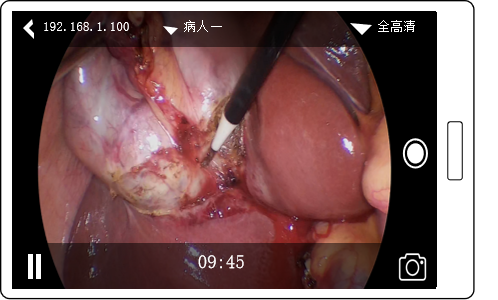

4K超清图像效果

企业微信截图_17496941442680.png

智能曝光

通过系统的智能曝光算法,在显微镜不同的光照环境,以及不同的手术器械介入,对画面曝光智能调整,让医生不再受到图像过曝的困扰。

企业微信截图_17496941466927.png

真实色彩

4K分辨率下,支持BT.2020广色域,专业的色彩调整,确保色差△C00<3,让医生所见即所得。